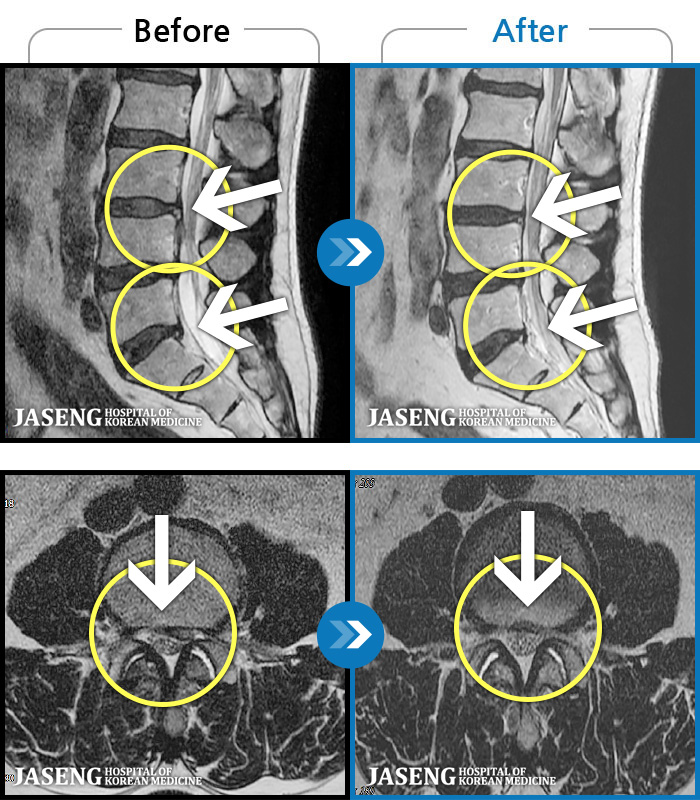

[] 03.04.01~09.11.01

ȯںп Ǹ ǿ ԿǾ, ο ġ ۿ Ƿ ġḦ Ͻñ ٶϴ.